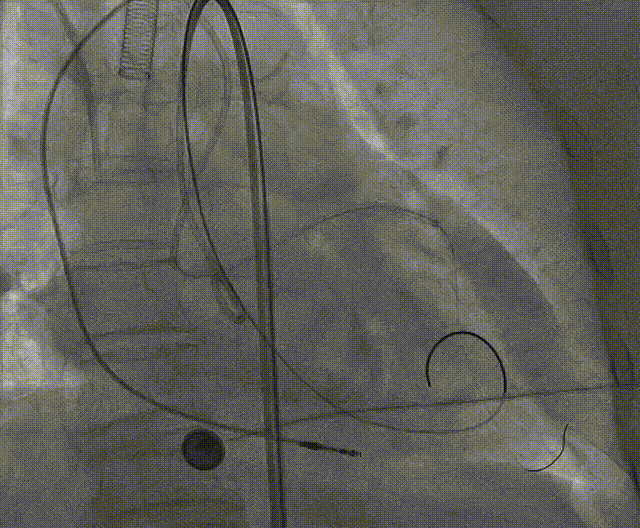

手术流程概括

零位定位开始释放,一次释放,零位释放位置良好,决定完全释放。

释放后多体位观察造影,瓣膜位置良好,展开良好,轻微瓣周漏。